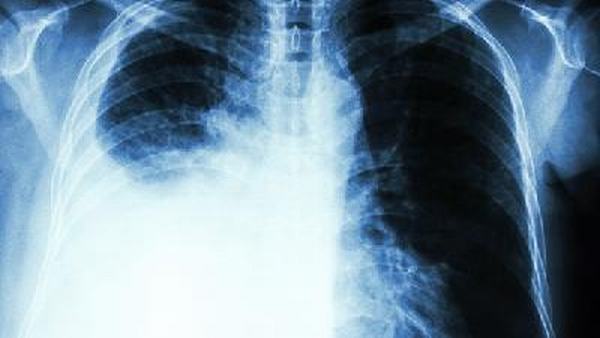

特发性肺纤维化(Idiopathic Pulmonary Fibrosis,IPF)是一种以肺部弥漫性纤维化为特征的慢性进展性疾病,其原因尚不明确。IPF患者常表现为进行性呼吸困难、咳嗽等症状,并且没有明显特征性临床征象。尽管IPF目前难以治愈,然而,合理的常规护理可以缓解症状、延缓疾病的进展,并提高生活质量。

最后,定期进行复诊和规范用药是IPF患者常规护理的重要内容。患者应定期复查肺功能、胸部CT等检查,密切监测疾病的进展情况。同时,患者应按医生建议规范用药,如应用抗纤维化药物,以延缓疾病的进展。